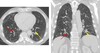

What pathology is seen here?

Bronchiectasis ## Footnote -Seeing cysts (advanced) -Fibrosis throughout the lungs

108

Bronchiectasis ## Footnote -Airway very dilated -Walls are normal thickness

109

Bronchiectasis ## Footnote -Signet ring appearance (ring is the bronchus, stone sitting on the ring is the blood vessel beside)

110

Bronchiectasis ## Footnote -Large airways -Collection of mucus in airways

111

Bronchiectasis; String of pearls